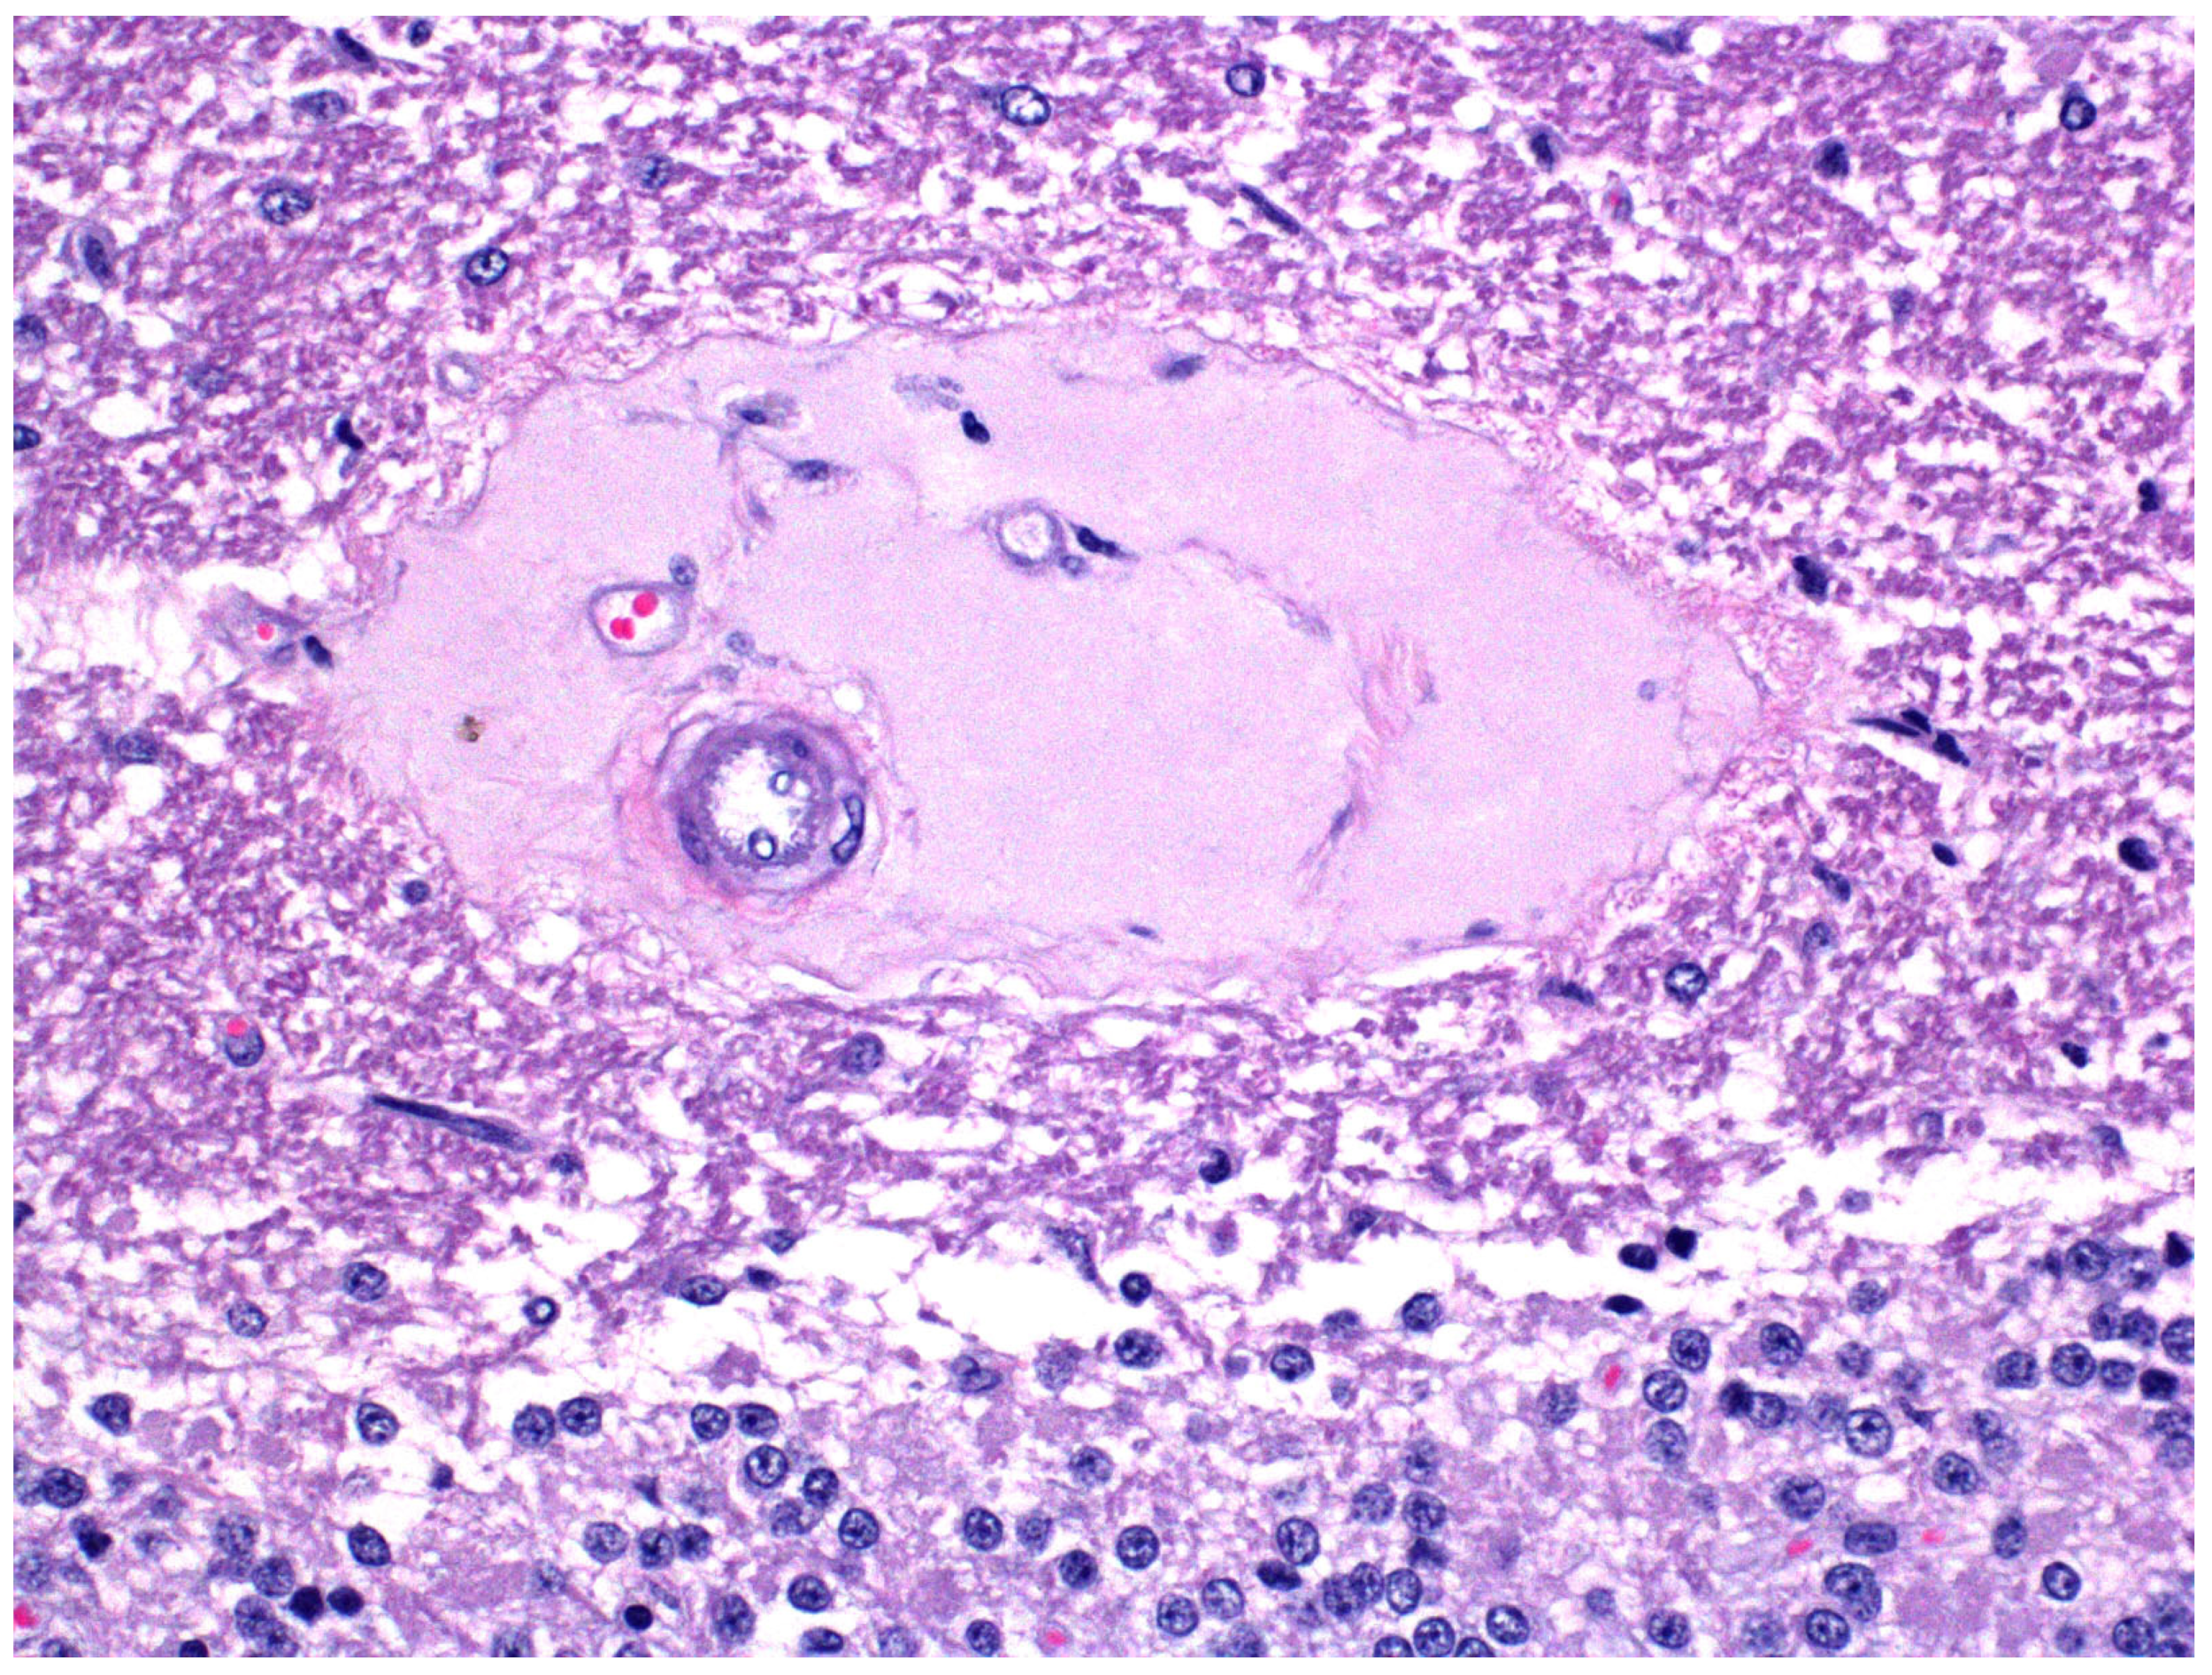

- Manavis, J.; Blumbergs, P.; Jerrett, I.; Hanshaw, D.; Uzal, F.; Finnie, J. Heterogeneous immunoreactivity of axonal spheroids in focal symmetrical encephalomalacia produced by Clostridium perfringens type D epsilon toxin in sheep. Vet. Pathol. 2022, 59, 328–332. [Google Scholar] [CrossRef]

- Vandevelde, M.; Higgins, R.J.; Oevermann, A. Veterinary Neuropathology. Essentials of Theory and Practice; Wiley-Blackwell: Ames, IA, USA, 2012; pp. 108, 187–189. [Google Scholar]